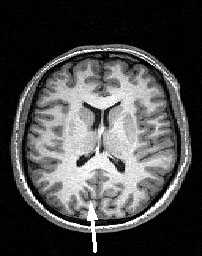

МРТ головного мозга. Аксиальный срез. Центральная борозда (стрелки).

МРТ головного мозга. Аксиальный срез на уровне крыши боковых желудочков. Центральная борозда (стрелки).

МРТ головного мозга. Границы лобной и теменной долей в аксиальной плоскости.